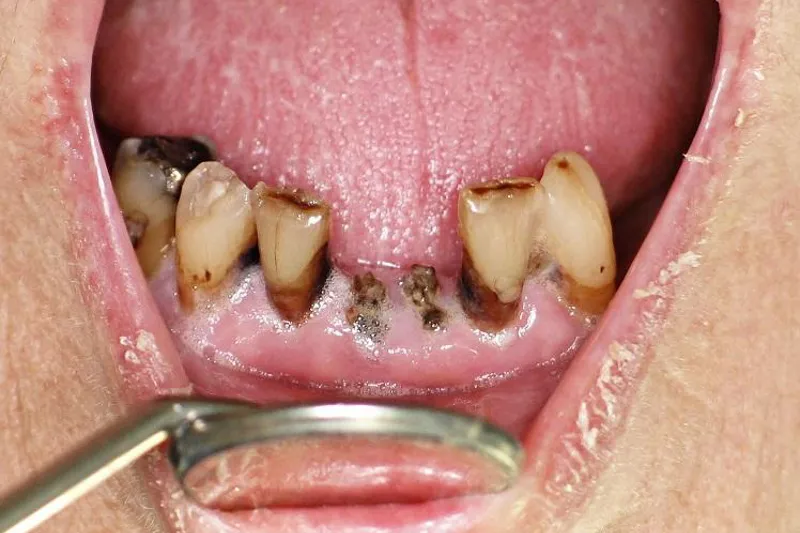

Strålerelateret caries er en overset komplikation efter strålebehandling af cancer i hoved-hals-regionen, men ifølge brasilianske forskere er strålerelateret caries den hyppigste årsag til tandtab efter afsluttet strålebehandling. Forskerne har fulgt 66 patienter i gennemsnitlig fire år efter endt strålebehandling.

67,8 % af tænderne blev ekstraheret som følge af fremskreden strålerelateret caries

Alle patienter havde inden behandlingen gennemgået en odontologisk sanering, hvor bl.a. tænder med fremskreden parodontitis eller caries blev ekstraheret, og de fik hyppige odontologiske kontrolundersøgelser i opfølgningsperioden. Af de 1.071 tænder, der var til stede ved strålebehandlingens afslutning, måtte yderligere 656 ekstraheres efterfølgende (9,9 tænder pr. patient). 67,8 % af tænderne blev ekstraheret som følge af fremskreden strålerelateret caries, mens 29,1 % blev mistet på grund af parodontitis og/eller apikal parodontitis.

Forfatterne anfører, at den reducerede spytsekretion efter bestråling af hoved og hals kan fremme cariesudviklingen, fordi den selvrensende evne, bufferkapaciteten, mængden af antimikrobielle antistoffer og proteiner samt remineralisationen dermed svækkes.